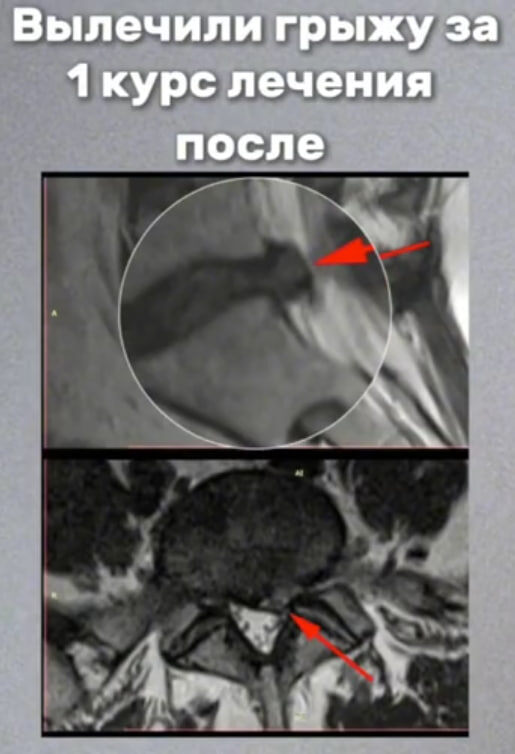

После